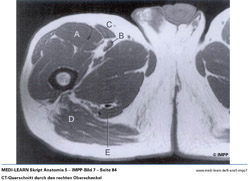

• CT-Querschnitt durch den rechten Oberschenkel